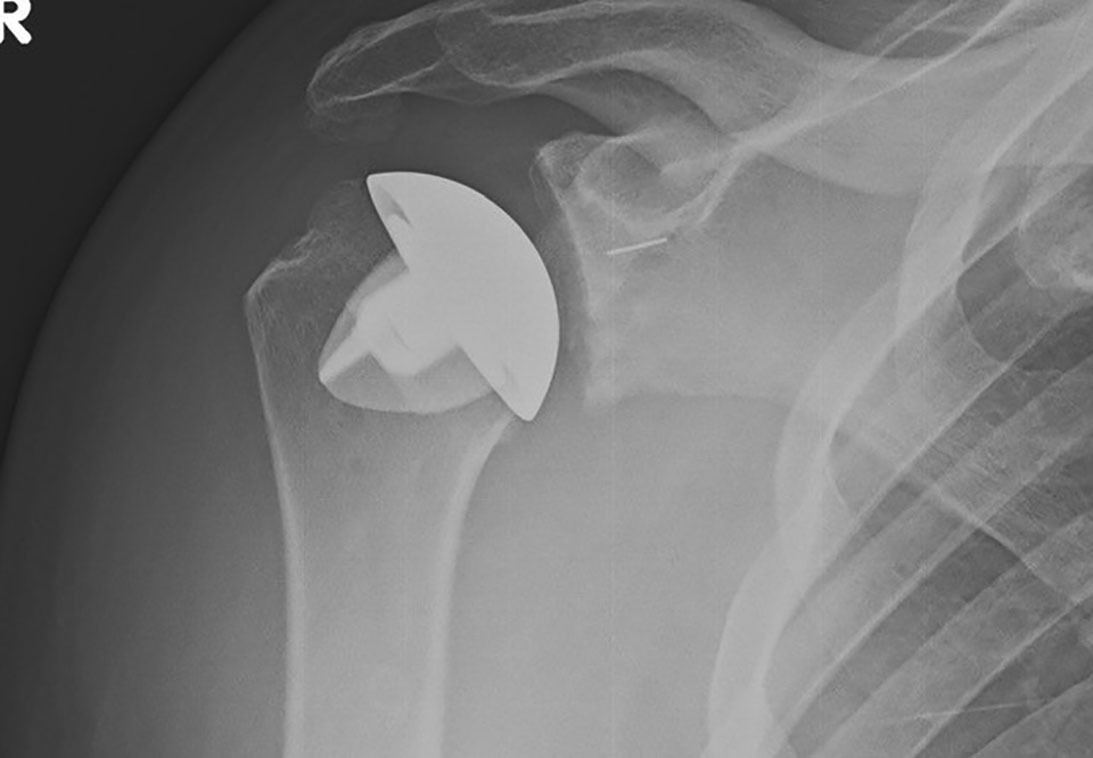

• Advancements in Anatomical Shoulder Replacement Surgery Improve Surgical Factors and Long-term Patient Outcomes

This three-part series covers recent advancements in total shoulder replacement, including efforts to facilitate surgical techniques, reduce complications and costs, and improve patient experiences and outcomes.